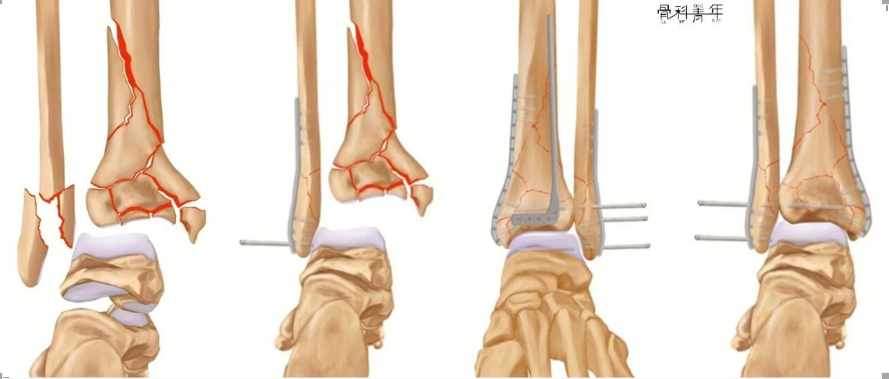

桡骨远端骨折的诊断与治疗

腓骨髓内钉固定减少一个切口可行吗?